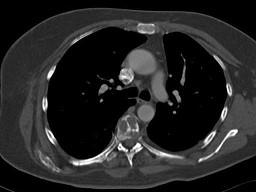

问题 女,47岁,背痛半月余,2个月前被诊断为乳腺癌肝转移,请结合影像学检查,选出最可能的诊断 ( )

选项 A、椎体压缩骨折 B、脊椎退行性变 C、脊椎转移瘤 D、化脓性脊柱炎 E、脊椎结核

答案 C